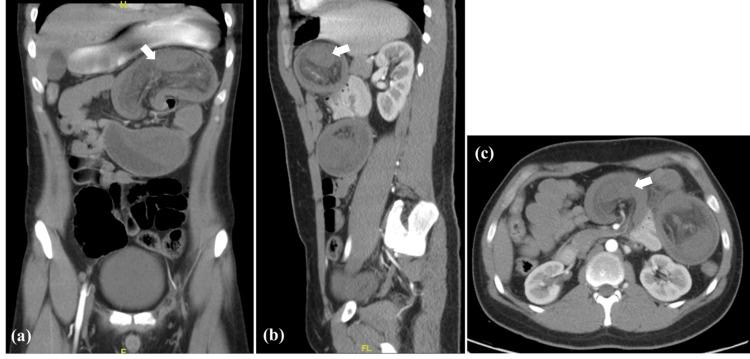

Intussusception is considered one of the rare causes of intestinal obstruction in adults compared to pediatric patients. It usually presents with non-specific clinical manifestations ranging from mild recurrent abdominal pain to severe acute abdominal pain. The non-specificity of its symptoms makes it difficult to diagnose preoperatively. As 90% of adult intussusceptions are due to a pathological lead point, this prompts the underlying medical condition to be identified. We herein report a rare case of a 21-year-old male with atypical clinical features of Peutz-Jegher syndrome (PJS), presenting with jejunojejunal intussusception as a result of a hamartomatous intestinal polyp. A preliminary diagnosis of intussusception was made after an abdominal computed tomography (CT) scan and was confirmed intraoperatively. Postoperatively, the patient's condition improved steadily, and he was discharged with a referral to the gastroenterologist for further assessment.

与儿科患者相比,肠套叠被认为是成人肠梗阻的罕见原因之一。它通常表现为非特异性临床表现,从轻度反复腹痛到严重急性腹痛不等。其症状的非特异性使得术前诊断困难。由于90%的成人肠套叠是由病理性引导点引起的,这促使识别潜在的疾病状况。我们在此报告一例罕见的21岁男性,具有黑斑息肉综合征(PJS)的非典型临床特征,因错构瘤性肠息肉导致空肠空肠套叠。腹部计算机断层扫描(CT)后初步诊断为肠套叠,并在术中得到证实。术后,患者病情稳步改善,出院时转诊至胃肠病学家处进行进一步评估。